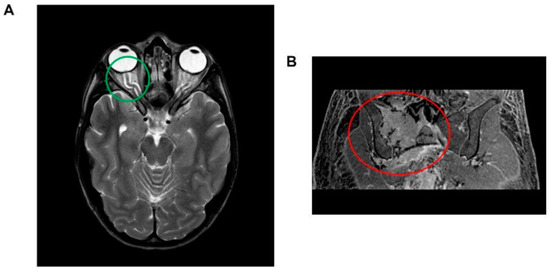

Figure 1.

(A) Brain magnetic resonance imaging (MRI) illustrating indirect indicators of intracranial hypertension. Notable features include the tortuosity of the optic nerve accompanied by sheath enlargement and the intraocular protrusion of the optic nerve head, which is coupled with posterior scleral flattening (highlighted within the green circle). Additionally, a significant enhancement of the optic disc is observed. (B) Abdominal magnetic resonance imaging (MRI) depiction of a lesion located at the right hip, exhibiting transverse diameters of 70 × 66 mm. The lesion is characterized by a composition of both osteolytic and osteosclerotic components (encircled in red).

Abdominal MRI revealed hepatosplenomegaly, pelvic free fluid, and a sizable lesion (transverse diameters 70 × 66 mm) in the right hip bone (Figure 1B). A whole-body computed tomography (CT) scan showed that the hip bone lesion had mixed characteristics—including both osteolytic and osteosclerotic components—and was associated with other lesions in both the ipsilateral and contralateral hip bones. A CT-guided biopsy of the lesion confirmed plasma cell dyscrasia. Staging investigations—including superficial and deep lymph node ultrasounds and bone marrow histological and cytological examinations—revealed normal findings. A positron emission tomography scan confirmed high glucose uptake in the hip bone lesion. Notably, the patient exhibited significantly elevated serum VEGF levels (>8000 pg/mL). Based on these clinical and laboratory findings, a diagnosis of POEMS syndrome was established.